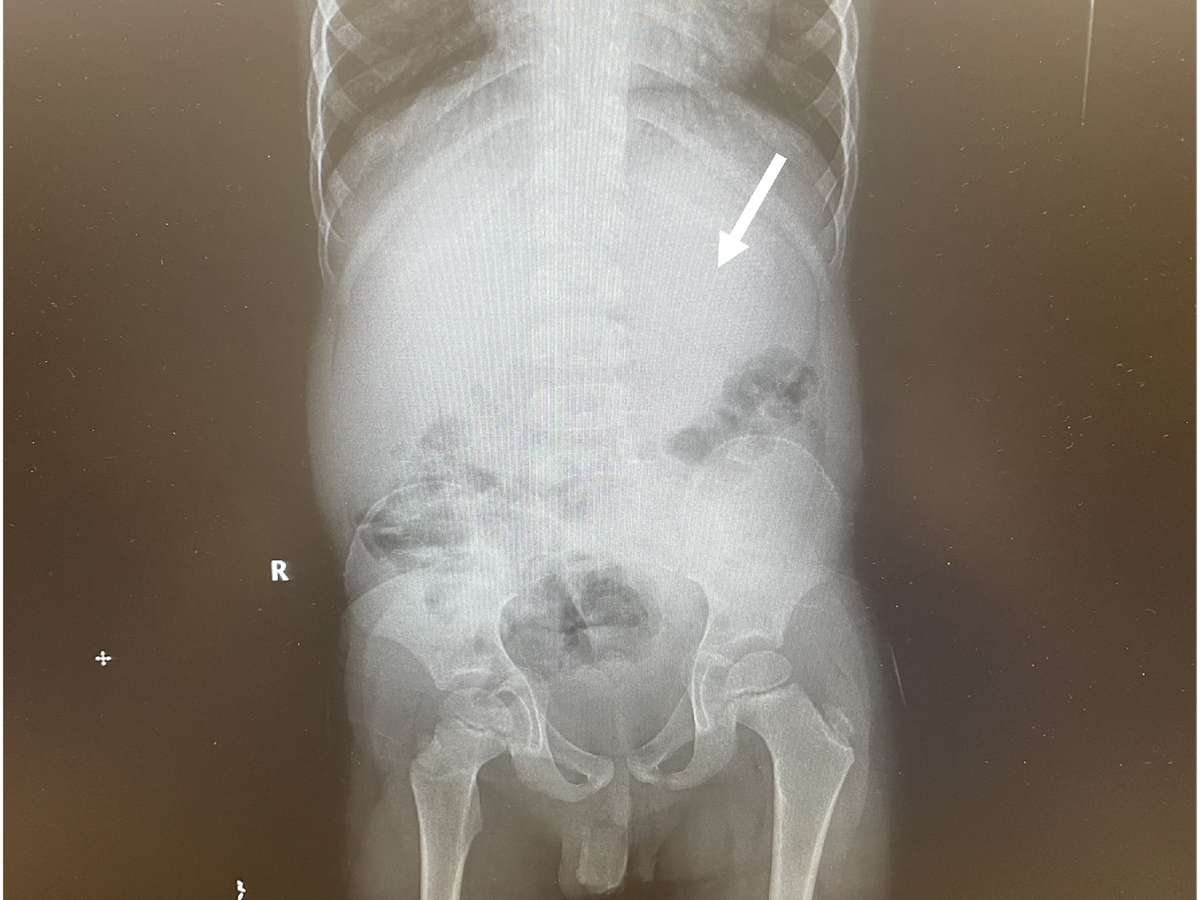

Os exames do garoto de Ohio revelaram que ele tinha um grande acúmulo de bezoar ocupando 25% do seu estômago. A solução foi puxar parte por parte da massa de volta pela garganta e pelas passagens do esôfago (canal que conduz o alimento até o estômago).

O menino precisou permanecer deitado de costas com um esofagoscópio, tubo de metal oco, posicionado em sua garganta. Em "várias passadas" e com auxílio de outros instrumentos, como pinças, os pedaços foram removidos pela equipe médica, que divulgou o caso na JEM Reports no início de maio.